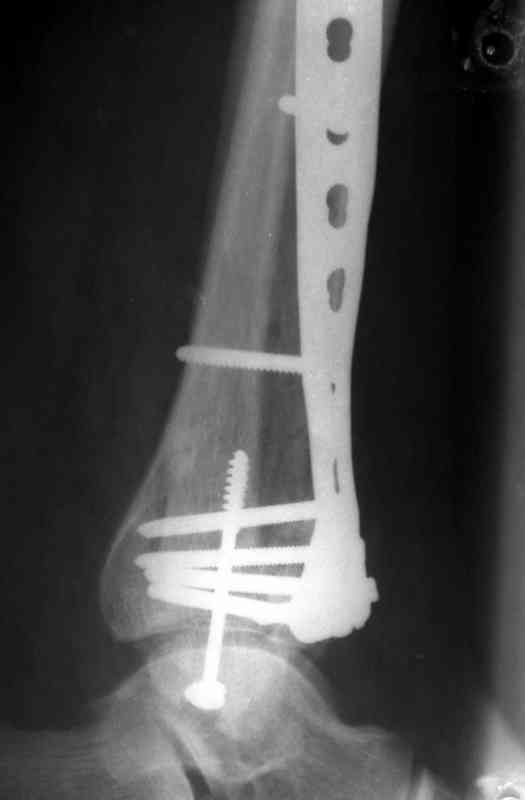

На рентгенограммах типичный перелом пилона по типу С-3. есть опыт до 100 открытых опреаций у нас в клинике. 20 примерно в год. Принцип один -все внутрисуставные переломы нуждаются в открытой репозиции и внутренней стабильной фиксации. При поступлении КТ не надо, так как получается только нагромождение костей. Истинной картины нет. Главное восстановить длину малоберцовой кости - это ключ к успеху. При поступлении меньше всего надо думать о сосудистых расстройствах, т.к. сама операция и репозиция даже сначала частичная даёт улучшение сосудитых нарушений. Причём очень быстро. Операция в 2этапа. При поступлении доступ позади наружной лодыжки, причём обязательно. После этого репозиция малоберцовой кости и фиксация пластиной 1/3 трубки под винт 3,5. Дренаж и любой аппарат наружной фиксации. Затем после спадения отёка на 5-7-10 день аппрат снимается и дугообразный разрез спереди от медиальной лодыжки 10-12 см. Главной чтобы расстояние между 1 и вторым разрезом было не меньше 7-8 см. Тогда не будет некрозов лоскутов. Таранная кость используется как матрица на неё укладываются отломки и фиксируются пицами. Ренг-контроль. Отломки лежат все отдельно, но ничего не высыпется. При переломах С-3 всегда нужна костная пластика (из крыла). Фиксация пластиной лист клевера простой или LCP. Гипс не нужен. Дренаж до 48 часов. Операция длится 3-4 часа обязательно без жгута. Посылаю примерно такой же случай.

Посылаю результат лечения предыдущего больного через год.

С уважением Дрягин

Ja operiroval bolnogo po Vashemu, hotia sam ni ochen' ubezden' v itom, t.k. bolnoi otkazalsa na proch' ot ex.fix, ja emu sdelal ORIF + Kostnia plastika, snimky prelogiottsa,